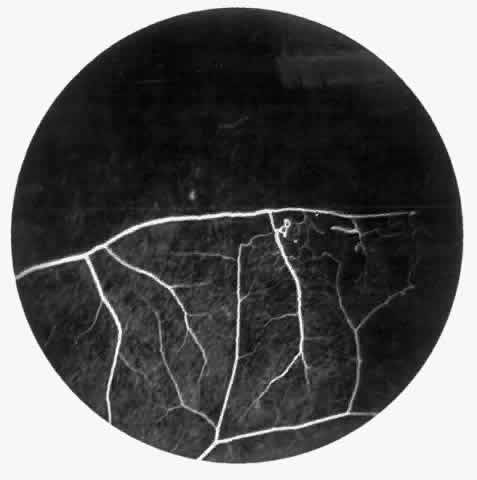

STAGE II: PERIPHERAL ARTERIOLAR-VENULAR ANASTOMOSES. Following occlusion of the terminal arterioles, anastomotic channels form to channel the blood from the occluded arteriole to the nearest venules. These anastomoses form at the interface between the perfused and nonperfused retina. Most likely, they are dilated preexisting capillaries rather than new vessels, since they do not leak on fluorescein angiography. The redirection of blood flow is probably due to hydrostatic forces (Figs. 22 and 23).

STAGE III: PRERETINAL NEOVASCULARIZATION (PROLIFERATIVE SICKLE RETINOPATHY). “Sea fan”-shaped neovascularization typically develops on the venular side of an arteriolar-venular anastomosis, mimicking the normal development of retinal capillaries (Fig. 24).125 A lowered oxygen tension and angiogenic factors released on the venular side may be the stimulus for neovascular growth.125,126 In most instances, the direction of growth is toward the ora serrata, from the perfused retina toward the nonperfused retina. Presumably, this represents an abortive attempt to revascularize the nonperfused retina, initiated by vasoproliferative factors.

The characteristic neovascular lesions of PSR are called sea fans because they resemble the marine invertebrate Gorgonia flabellum.70 They tend to occur more commonly in the temporal periphery, but they have been reported to occur in the temporal macula in the presence of extensive nonperfusion.130,133 Initially they grow on the surface of the retina, but they often become elevated into the vitreous and adhere to a partially detached posterior hyaloid.114 It may be difficult to visualize small sea fans ophthalmoscopically; however, fluorescein angiography clearly demonstrates leakage of dye into the vitreous (Fig. 25). The feeding arteriole is usually more tortuous than the draining venule (Fig. 26). Early on, the neovascular lesion is fed by a single arteriole and drained by a single venule, but with time, additional arterioles and venules become arborized within the lesion (Fig. 27).129 Growth of the sea fan often occurs circumferentially, rather than radiallyÜmh- 1Ý, toward the ora serrata. Progressive circumferential growth may lead to neovascular lesions extending around the entire periphery. As it matures, a white fibroglial mantle often covers the neovascular tissue (Color Plate 2B).